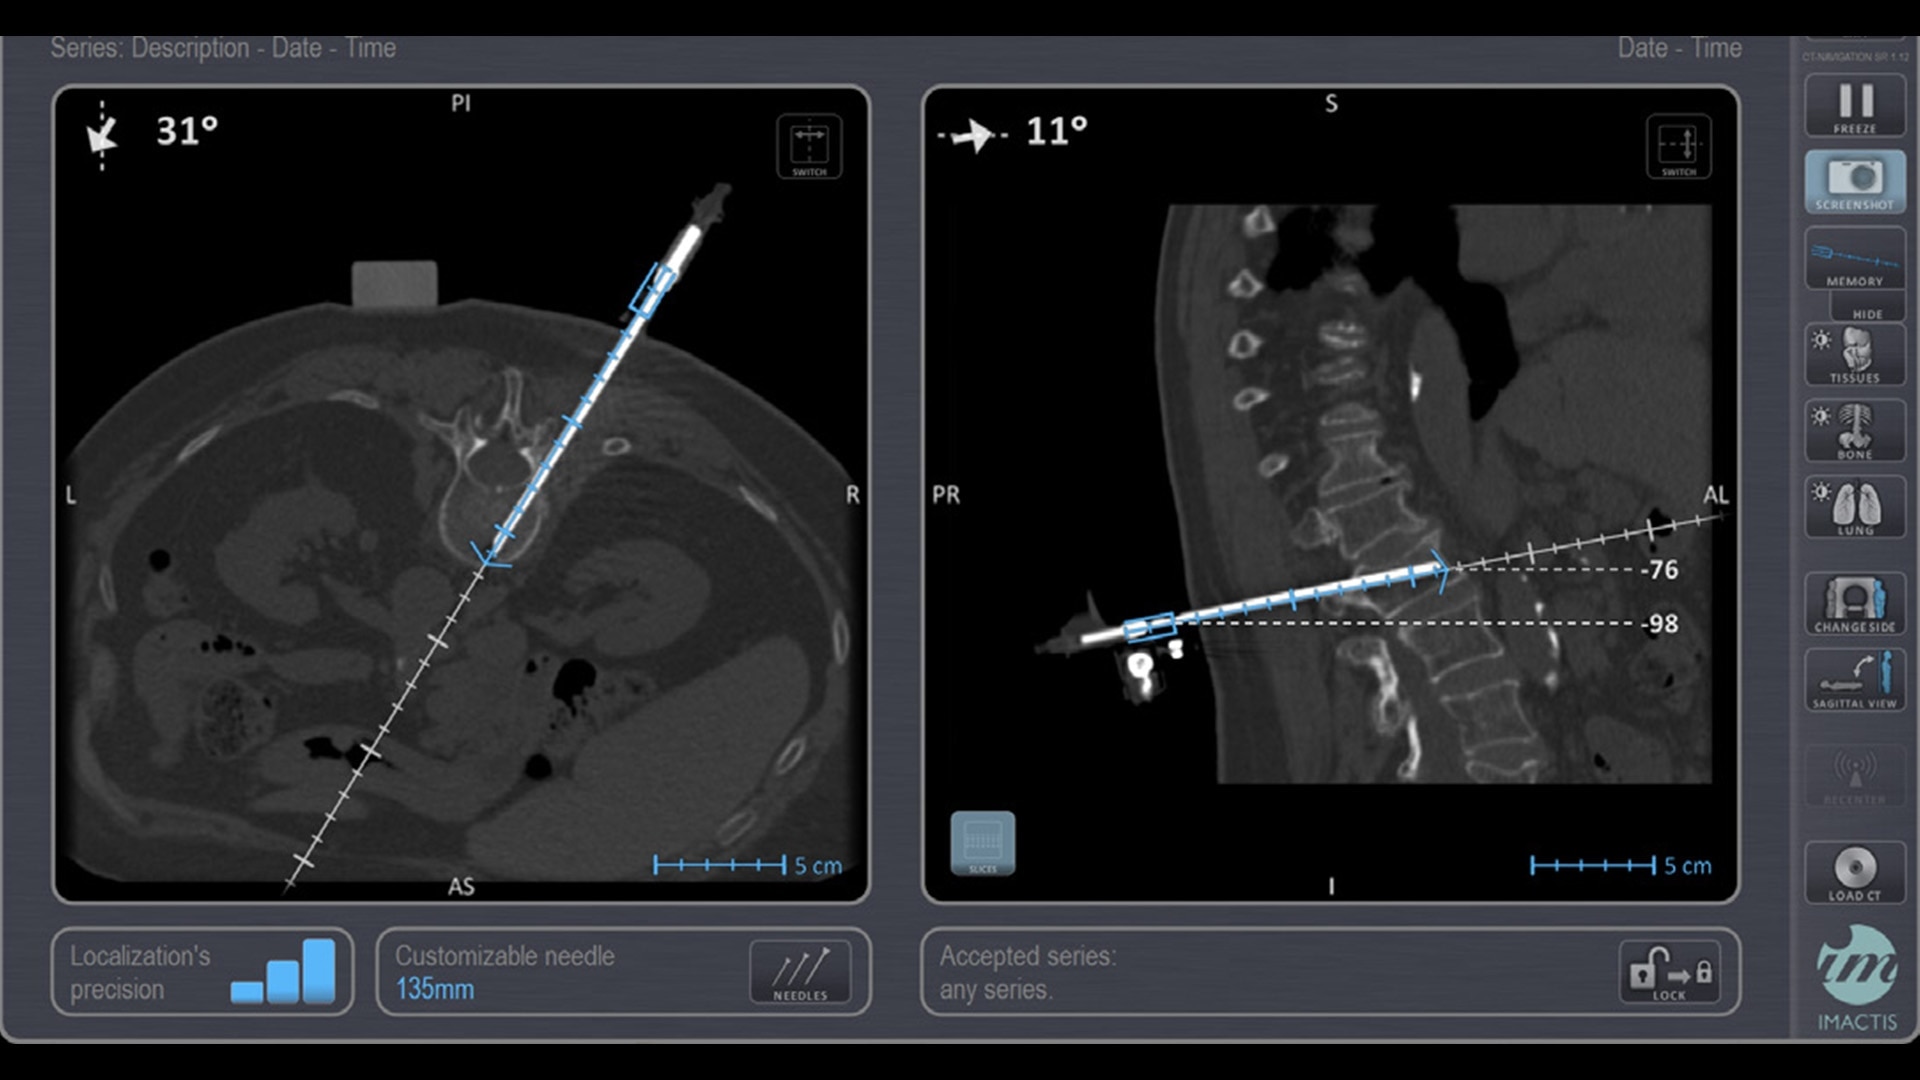

In interventional radiology, the success of the percutaneous procedure depends on correct needle positioning. The Imactis system helps the radiologist place one or more needles with great accuracy, in less time and with fewer control scans.

The CT navigation solution optimizes the efficiency and potentially helps to improve clinical outcomes of biopsies, thermoablations, drainages, infiltrations, electroporations and osteosynthesis.

With real-time image reconstruction, live interactive navigation and no limit in angulation, the optimal clinical choices are clear.

Live 3D needle tracking, precise reproduction of your planned trajectory and continuous needle depth measurement help ensure optimal needle placement.